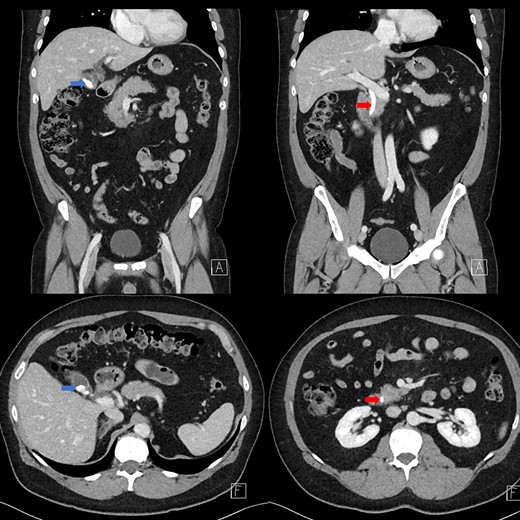

Portal venous contrast enhanced computed tomography (CT) of the abdomen revealed a layered dependent hyperattenuating material within the biliary tree (Fig. 1). The common bile duct (CBD) was dilated measuring 7.5 mm in diameter and filled along its course with radiodense material. Mild distention of the cystic duct and intrahepatic biliary tree were also noted with a 4 mm calculus in the CBD at the level of the duodenal ampulla (Fig. 2). There was no radiological evidence of cholecystitis.

Contrast-enhanced CT demonstrating limy bile within the gallbladder neck (left image) and CBD (right image).

CT demonstrating an obstructing calculus (right image) present within the CBD distinct from the limy bile (left image) (WW 2249, WL 450).